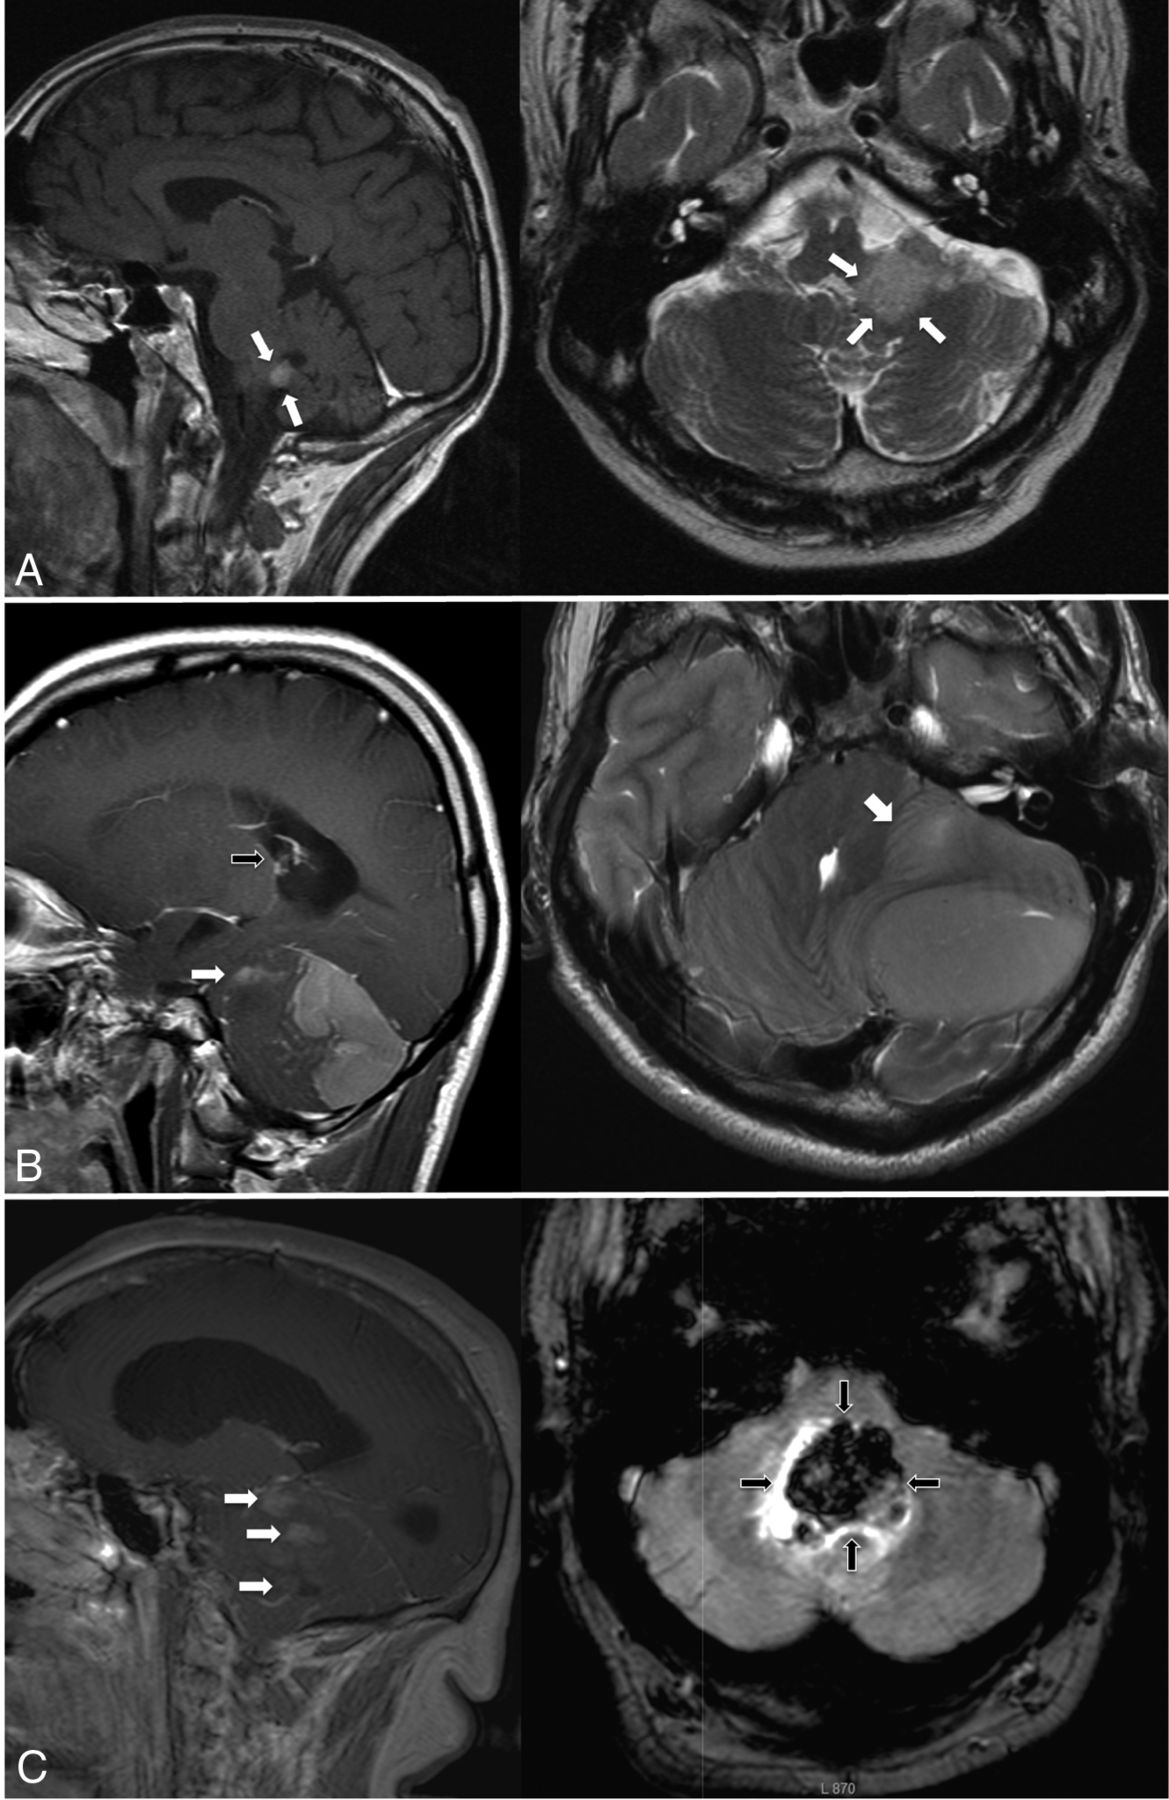

The differentiation of SHH-activated and non-SHH/non-WNT Group 4 lesions was possible on the basis of edema volumes (SHH-activated medulloblatoma: median edema, 5.1 cm3; 95% CI, 3.3–8.0 cm3; Group 4 median edema, 1.2 cm3; 95% CI, 0.0–6.9 cm3; AUC, 0.85 [95% CI, 0.63–1.0; P = .02]), while tumor at the fourth ventricle (SHH-activated medulloblastoma, 3 of 19 cases; Group 4, three of 5 cases; AUC, 7.21; 95% CI, 0.39–1.0), contact with the lower rhombic lip, and the presence of hemorrhage (both biomarkers: SHH-activated medulloblastoma in 0 of 19 cases; Group 4, two of 5 cases; AUC, 0.70; 95% CI, 0.39–1.0) were less reliable and not significant (P = .14, .18, and .18, respectively). A visualization of MR imaging biomarkers for all 3 genetically defined medulloblastoma entities is presented in Fig 1.

Characteristic imaging features of genetic medulloblastoma entities. Sagittal sections on the left; transverse sections on the right. A, Typical WNT-activated medulloblastoma, relatively small, in contact with the fourth ventricle (tumor margins marked with white arrows), no hydrocephalus. B, SHH-activated medulloblastoma with large tumor volume and macrometastases (sagittal image, white arrow) and large edema volume (transverse image, white arrow) and hydrocephalus (sagittal image, black arrow). C, Non-SHH/non-WNT Group 4 tumor showing macrometastases (sagittal image, white arrows), hydrocephalus, and hemorrhage (transverse image, black arrows) as distinguishing features.